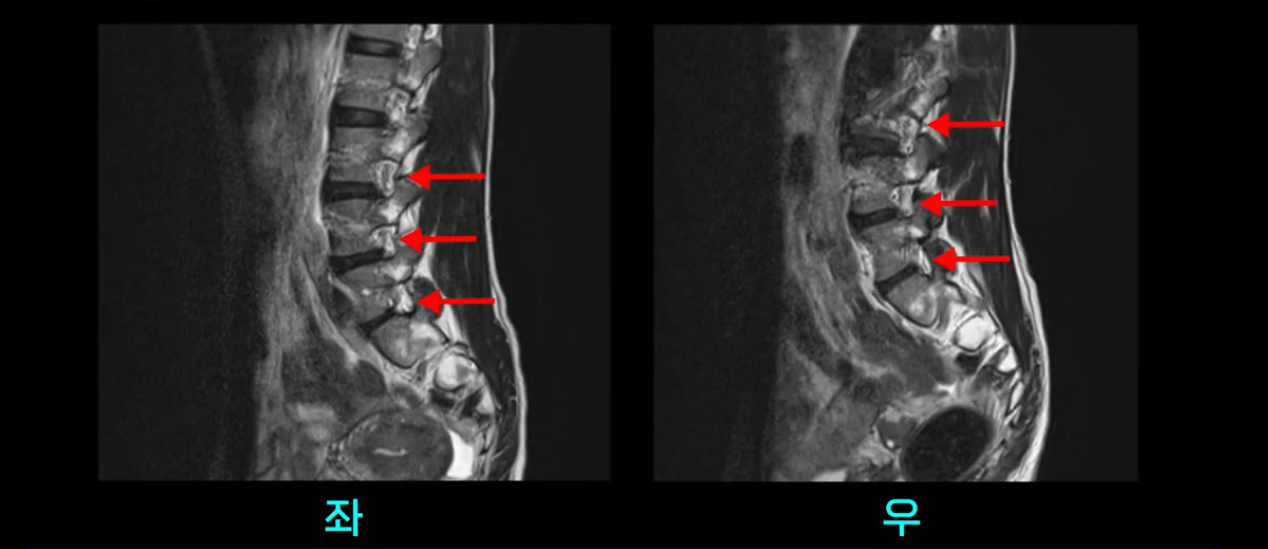

이분 MRI를 보시면 두 마디의 퇴행성디스크가 있습니다. 그리고 디스크가 조금씩 밀려 나와 있고요. 그런데 디스크 탈출 정도는 두 마디 다 심하지 않습니다. 4번 5번에는 디스크 탈출이 약간 있고,

척추관협착도 약간 진행이 되고 있고요.

5번 1번은 디스크 탈출이 가운데 쪽으로 살짝 있습니다.

또한 양쪽 신경 가지가 빠져나가는 추간공은 매우 넓은 상태입니다.

중요한 것은 이 정도 경미한 탈출과 협착으로는 양쪽 다리가 저리고 아플 수가 없습니다.

그리고 만약에 이 디스크가 급성으로 찢어진 것이라면 아주 심한 디스크성 통증이 있겠죠. 기침이나 재채기를 하면 심하게 아프고 허리를 조금만 구부려도 아주 날카로운 통증들이 생길 겁니다. 그런데 이분은 이런 증상이 전혀 아닙니다. 디스크의 돌출 정도와 협착이 전혀 심하지 않기 때문에 이분이 가지고 계신 양쪽 다리 저림, 특히 이분은 누워있을 때도 양쪽 다리가 저리다고 하는데, 디스크 때문에 그런 증상은 생길 수가 없습니다. 또 이 디스크는 오래된 디스크, 이미 찢어진 섬유륜이 아문 디스크이고, 그러니까 이분은 기침이나 재채기를 못하는 증상이 없는 거죠. 그 다음에 허리를 구부릴 때 뻐근한 증상은 있지만 아주 날카로운 통증은 없습니다.

이분 MRI를 보시면 퇴행성디스크가 있고 약간의 협착이 있지만 이 정도의 퇴행성디스크와 협착으로는 신경이 눌려서 양쪽 다리가 저리고 아픈 증상이 나올 수가 없습니다. 그래서 MRI와 이 환자분의 다리 증상이 매치가 안 된다고 하는 의사들이 많은 겁니다.